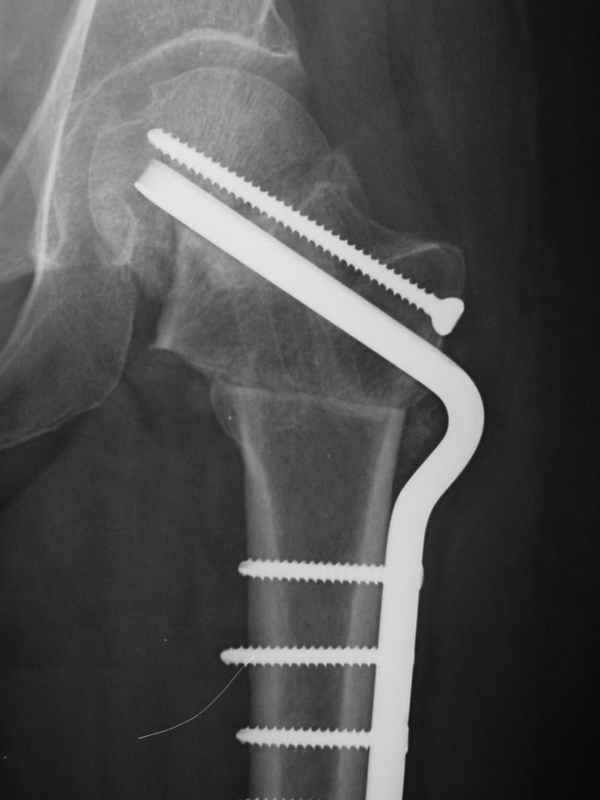

dhs will not correct improper biomechanical environment and may further compromise vascular

case provided s/p failed fixation